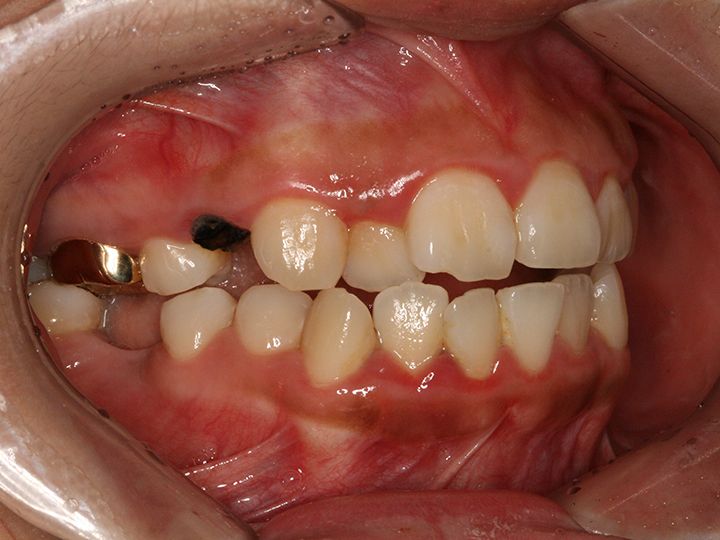

「ライムナム歯科病院」はラミネートやセラミックを使った審美治療、美白治療、インプラント、歯列矯正など、あらゆる歯の悩みに応える歯科病院です。2004年の開業以来、常に新しい技術と診療機器を取り入れ、韓国内外の患者の信頼を集めてきました。特に忙しい現代人の悩みである時間短縮治療メニューが充実。来院当日にできるだけ解決できるようなシステムを構築しています。独自の歯科技工所を持っているのもその理由のひとつ。また20年にわたるノウハウの蓄積を生かし、患者の負担を減らせるように痛みを減らす施術にも力を入れています。